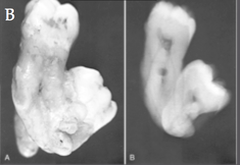

Compound and Complex Odontomas

Compound: Anterior of Max.; "Numerous small teeth" - see picture Complex: Post of Jaws; Mass